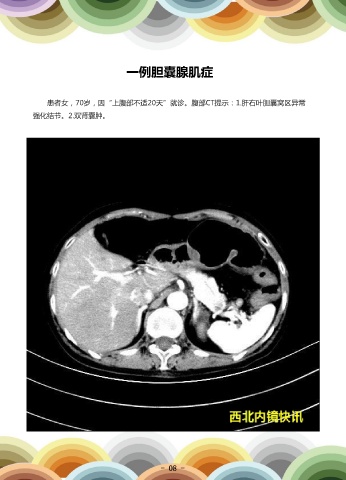

一例胆囊腺肌症

患者女,70岁,因“上腹部不适20天”就诊。腹部CT提示:1.肝右叶胆囊窝区异常                                      超声内镜示:胆囊底部低回声占位考虑腺肌症,符合早期慢性胰腺炎改变。患者在全

强化结节。2.双肾囊肿。                                                                   麻下行腹腔镜下胆囊切除术,手术顺利,术后病理示:慢性胆囊炎合并腺肌症及局灶纤维

组织增生。